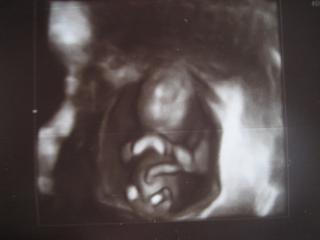

V cakarni sme pocuvali radio, islo nejake techno, a potom na ultrazvuku babo z nicoho nic mavalo rukami, nohami, akoby tancovalo, ale po chvilke prestalo a vtedy urobila tu foto. Tak potesi aj jedno, aj druhe, len nech je zdrave, to chce kazda mamka. A my, kedze sa nam roky nedarilo, o to viac ocakavame, a bude to prve vnuca na oboch stranach rodiny, tak si vies predstavit, ako kazdy len tuzi aby bolo krasne a zdrave. My sme pripraveni, ake Boh da, take bude, ved on vie, ale samozrejme, ze sa modlime za zdrave babatko.